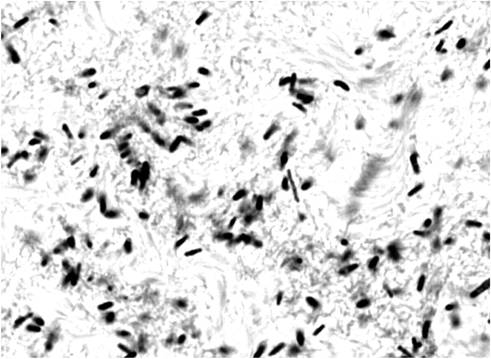

MORFOLOGIA SPECIEI CLOSTRIDIUM BOTULINUM

Este un bacil mare(0.5-2.4/2-22μ),drept sau usor incurbat,Gram pozitiv,mobil cu cili dispusi peritrih,necapsulogeni,sporogeni.Este sporogen,dupa formare sporul este oval,situate subterminal,are dimensiuni mai mare decat diametrul transversal al celulei pe care o deformeaza,dandu-i aspectul de sticla de lampa.La tulpinile de C.botulinum care apartine tipului G,celulele vegetative au dimensiuni mai mari, in timp ce la tulpinile care apartinand tulpinilor B si F, celulele vegetative au dimensiuni mai mici.